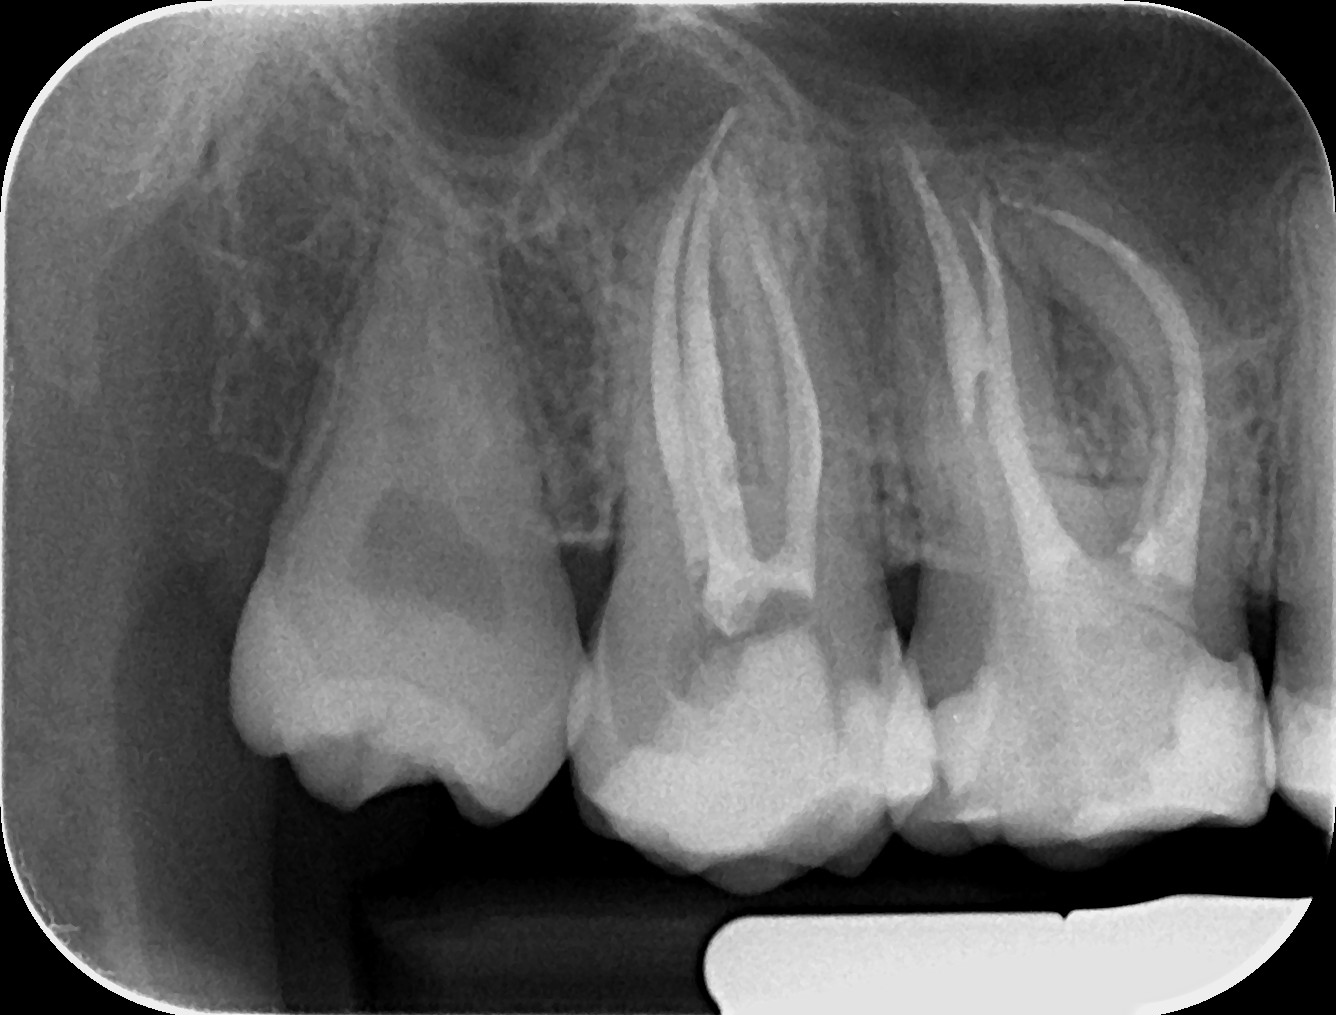

Pacienții necesită un tratament endodontic atunci când la nivelul camerei pulpare sau a canalului radicular există inflamație sau infecție, din cauza unei carii profunde, a unei fisuri sau provocată de un traumatism accidental. Poate fi realizat într-o singură ședință sau în mai multe, în funcție de complexitatea cazului.

În timpul tratamentului, medicul endodont curăță, dezinfectează, prepară canalele radiculare și obturează etanș spațiul creat. Dinții cu destrucții coronare masive necesită ranforsare cu pivoți de fibră de sticlă, iar ulterior vor fi șlefuiți și acoperiți cu lucrări protetice ce redau rezistența structurii dentare restante.